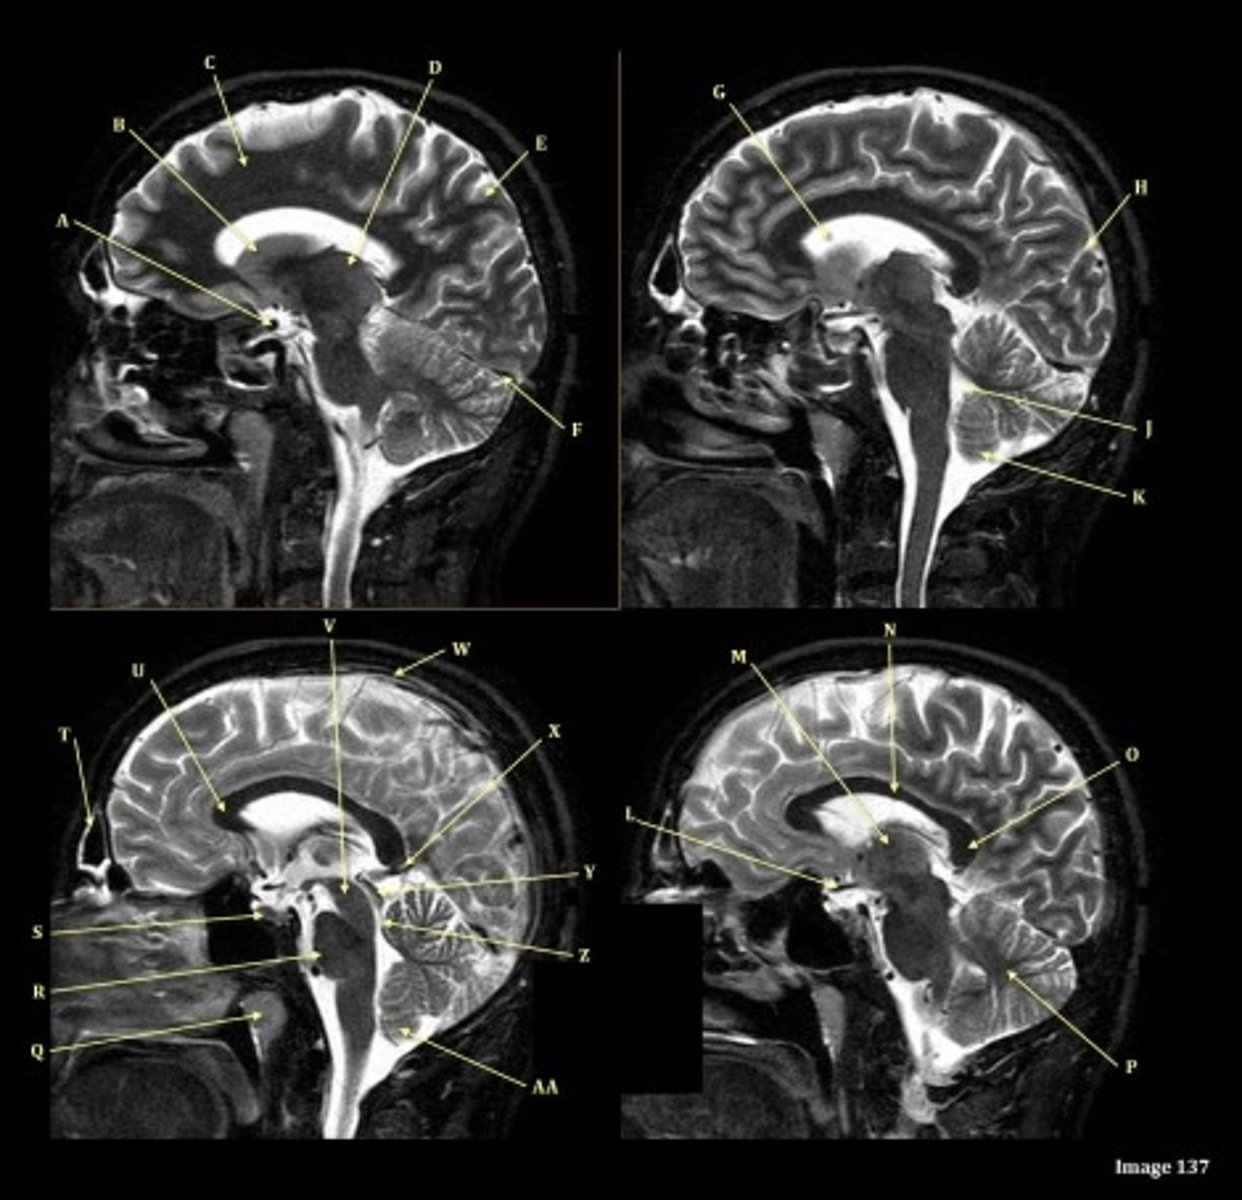

T2 FLAIR; Sagittal

A FLAIR (Fluid Attenuated Inversion Recovery) sequence is utilized to suppress signal from cerebrospinal fluid (CSF).

A

lateral ventricle

B

corpus callosum

C

thalamus

D- separates what

tentorium cerebelli- cerebrum (occipital and temporal lobes) from brainstem and cerebellum

E

fourth ventricle

F

medulla oblongata

caudate nucleus

third ventricle

D

lentiform nucleus

frontal sinus

A (region)

dark band is called?

basal ganglia region

internal capsule

posterior horn of lateral ventricle

anterior horn of lateral ventricle

white matter

gray matter

pituitary gland

corpus

fornix

internal carotid artery

straight sinus

G

H

lateral sulcus

L

optic chiasm

O

Splenium of corpus callosum

V

Cerebral peduncle

W

superior sagittal sinus

X

vein of galen

Y

Inferior colliculus of midbrain,

just inferior to pineal gland / superior to the cerebral aqueduct

Letter N in Image 137 is pointing to what type of tissue?

The corpus callosum is the only white matter tissue structure found in the midline sagittal slice of the brain.